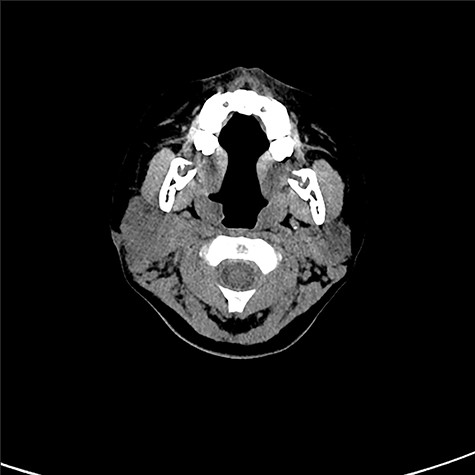

Three and a half years after the initial surgery, she presented with high fever and painful swelling of her right parotid area (Fig. 5). CT scan presented swelling of the parotid gland (Fig. 6). No cystic structure could be pointed out. Under general anesthesia, incision, cleansing and drainage were done. Staphylococcus aureus was identified in the pus. Decline of fever was obtained and remission of the abscess was seen.

Cystic lesion could not be observed by CT scan prior to the drainage.